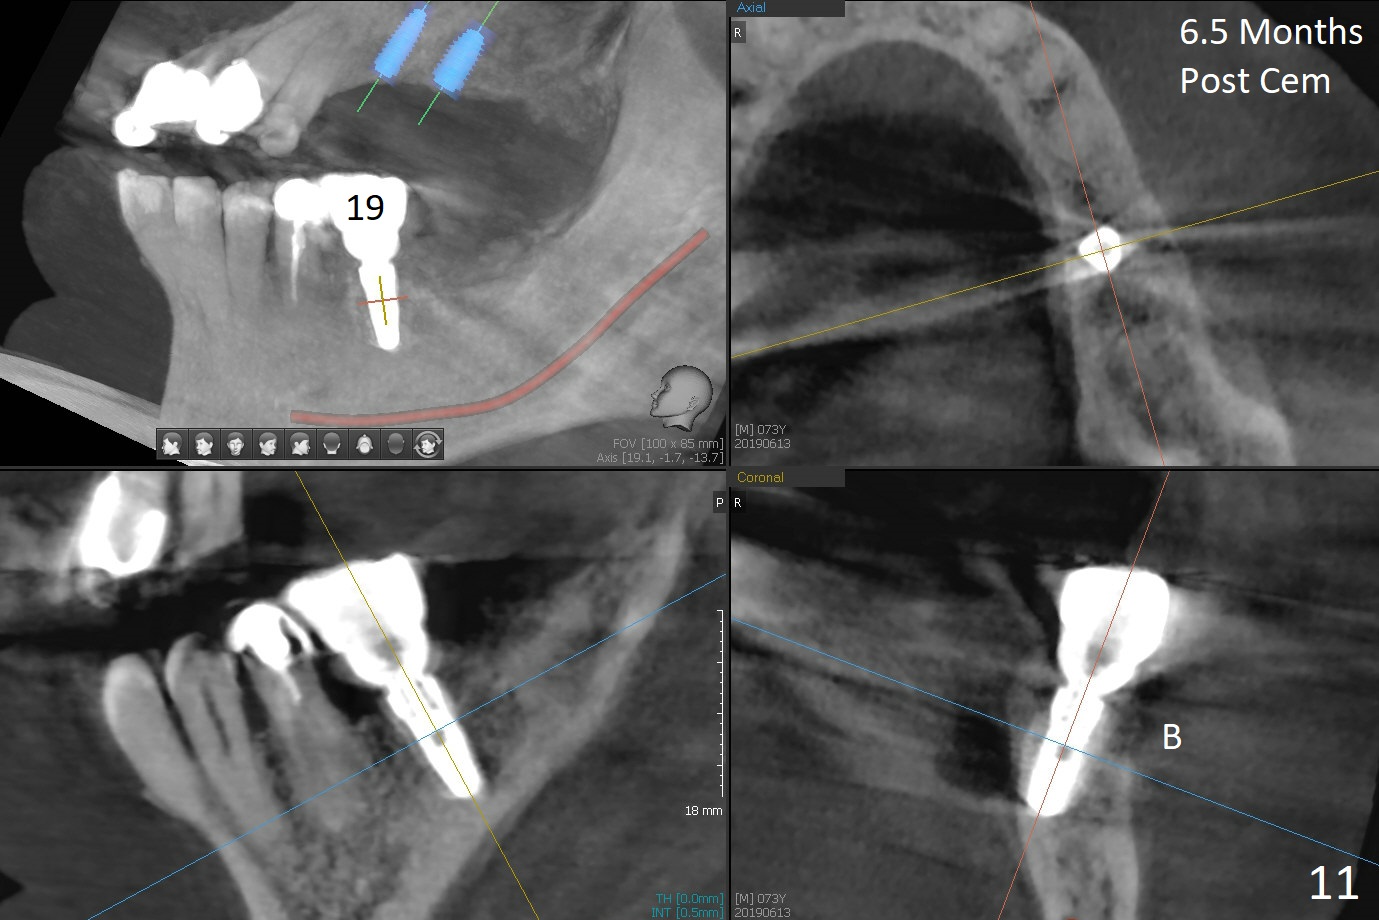

After extraction of the supraerupted tooth #19 with severe buccal gingival recession, the buccal and lingual plate are found to be lost. The sockets are fused and flat without the septum. The bone is hard and painful for the initial osteotomy with infiltration anesthesia (Fig.2). Following block anesthesia, the initial osteotomy depth extends to 8 mm (Fig.3,4). With apparent 4.9 mm clearance, the osteotomy is further extended to 10 mm. The osteotomy walls are apparently intact without severe hemorrhage after each drill. Due to the thick gingiva and severe bone loss, a 5x12 mm implant is intentionally placed 3 mm above the base of the socket bone (Fig.5,6 (yellow dashed line)). Vanilla Cortical and Cancellous allograft (Fig.6 *) is placed around the exposed implant and 7.8x5(6) mm abutment with 4 and 2 mm buccal and lingual gaps. Next collagen plug cut in strip is placed to fill the most coronal aspect of the socket (Fig.7 *). The buccal and lingual gingivae are approximated with sutures proximally. Finally periodontal dressing is applied. Since the Inferior Alveolar Canal is vague in intraop PAs (Fig.4,5), there is worry about potential nerve damage during and after osteotomy. This should be no issue if preop panoramic X-ray is reviewed with measurement (Fig.8). The bone graft appears to remain in place nearly 4 months postop (Fig.9). Two weeks later, he returns for impression. When the provisional is removed, the gingiva is unhealthy. Without the provisional and with improved oral hygiene, the gingiva is healthy one week later, but the tooth #18 is symptomatic. The latter is extracted with socket preservation (Fig.10 *). There is no apparent bone loss around the implant at #19 6.5 months post cementation (Fig.11).